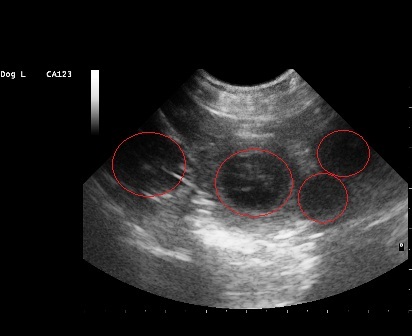

28.02.2013

Heute waren wir beim Ultraschall und Funny ist tragend !!!

Um den 6. April 2013 herum wird unser C-Wurf das Licht der Welt erblicken.